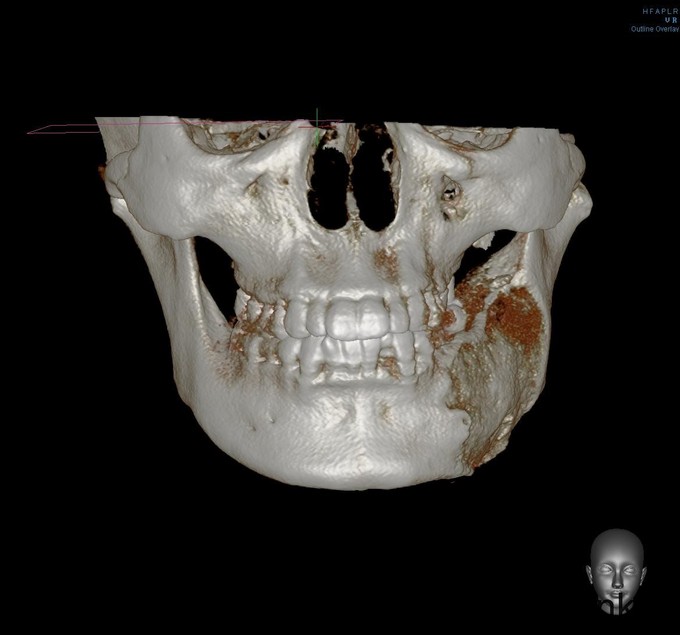

发现左下颌骨局部肿大6年,青年女患者,慢性病程。患者于6年前无明显诱因发现左下颌骨局部肿大,逐渐加重,无明显疼痛、口角麻木等不适。今为进一步治疗来我院就诊,门诊以"左下颌骨骨纤维异常增殖症"收入院

颌面部左右不对称,左下颌区较右侧肥大,开口型正常,开口度4.0cm,双侧关节无明显压痛、弹响,双侧髁突动度左右基本对称。左下颌骨约35至磨牙后区颌骨肿大,前庭沟变浅,同时舌侧可及肿大,质地硬,黏膜无破溃流脓,牙齿无明显松动。

诊断:左下颌骨骨纤维异样增殖症,全麻下行“左下颌骨整形行性切除+左下颌角修整术+邻近瓣转移修复术”